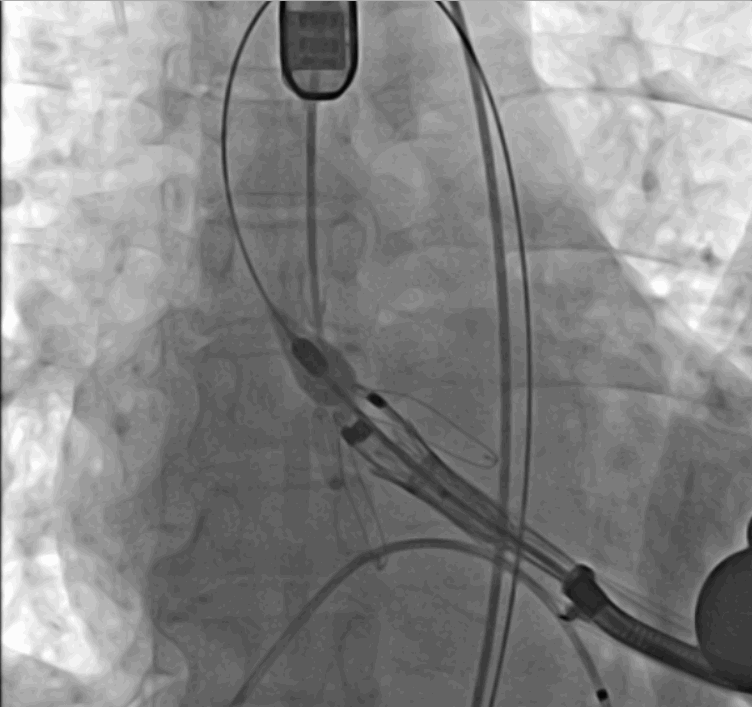

術中釋放定位鍵后DSA影像圖

術中瓣膜釋放過程